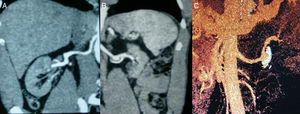

Despite intravenous hypotensive treatment (labetalol and nitrites), the patient's BP levels remained high. Therefore, it was decided to admit the patient to the Intensive Care Unit and start acute haemodialysis and plasmapheresis simultaneously on an emergency basis. A dilated eye fundi examination was performed and yielded a result consistent with grade IV hypertensive retinopathy. A kidney ultrasound showed destructured kidneys with poor corticomedullary differentiation and obvious asymmetry. An angio-CT scan (Fig. 1) ruled out left renal artery stenosis, but revealed an aneurysm in the left renal artery 2cm in diameter with a calcified and thrombosed wall. An ECG showed signs of left ventricular hypertrophy and diastolic overload, and an echocardiogram showed severe concentric LV hypertrophy with preserved systolic function.